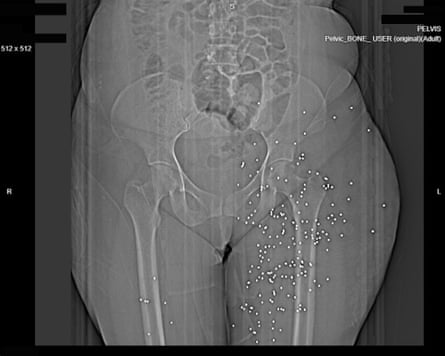

As well as the violence of the injuries, the X-rays are notable for the patterns they reveal: case after case shows patients shot at short to medium range in the face, chest and genitals.

At least nine have been shot in the genital or pelvic area with birdshot or, in three cases, with high-calibre rifles. One woman, middle aged, has been shot in the groin, and has almost 200 metal balls distributed into her thighs and pelvic area. A 35-year-old man has similar injuries: birdshot scattered across his groin. According to the medical analysis commissioned by the Guardian, the injuries could cause “serious disfigurement” as well as “serious injuries to the genitals, perineum, rectum, and urinary bladder”. They conclude: “Bladder and bowel incontinence, sterility and impotence are possible long-term outcomes.”